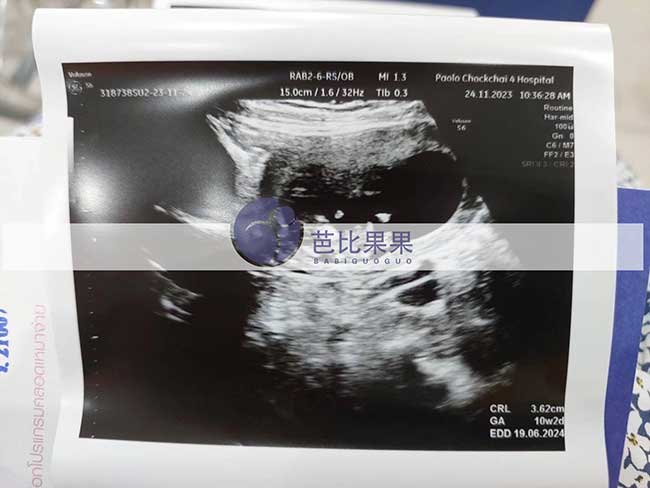

G先生泰国包成功的试管妈妈到医院做第10周B超孕检

安排我们G先生选择泰国包成功的试管妈妈到医院做第10周B超孕检,观测胎心发育正常